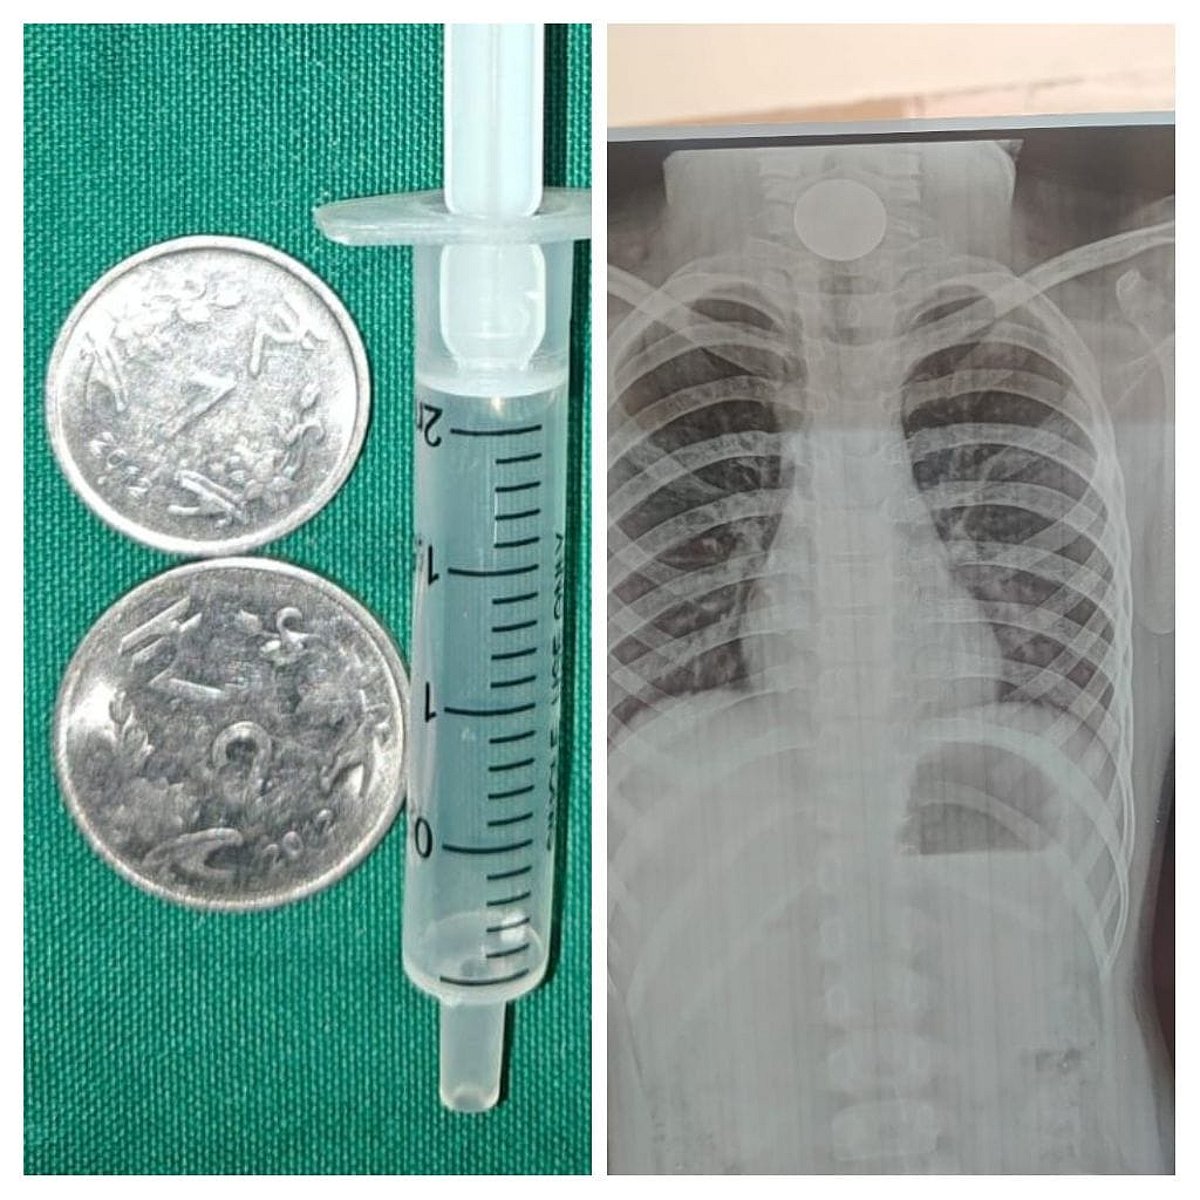

குழந்தையின் தொண்டையில் சிக்கிய நாணயங்கள் மற்றும் எக்ஸ்ரே படம்.